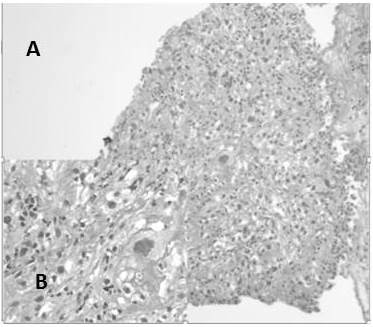

En el estudio los casos de carcinomas neuroendocrinos estuvieron representados en su mayoría por carcinomas neuroendocrinos de células pequeñas con 80 % de los casos (Figura 13), los carcinomas de células grandes (Figura 14) fueron 13,3 % y se observó un caso 6,7 % de tumor carcinoide típico (Figura 14) (Cuadro 10).

Los tumores neuroendocrinos mantuvieron la misma clasificación en tumores carcinoides típicos y atípicos (G1 y G2), carcinomas neuroendocrinos de células pequeñas y carcinomas neuroendocrinos de células grandes (G3) (30) en nuestra revisión obtuvimos 15 (7,4 %) casos de carcinomas neuroendocrinos, el tumor neuroendocrino más frecuente fue el carcinoma neuroendocrino de células pequeñas con 12 casos, se revisaron 2 casos de carcinoma neuroendocrino de células grandes y un tumor carcinoide típico. Estos resultados son similares a los encontrados por Machado A. (3) quien en su estudio concluye que el carcinoma neuroendocrino de células pequeñas es el tercer carcinoma más frecuente.